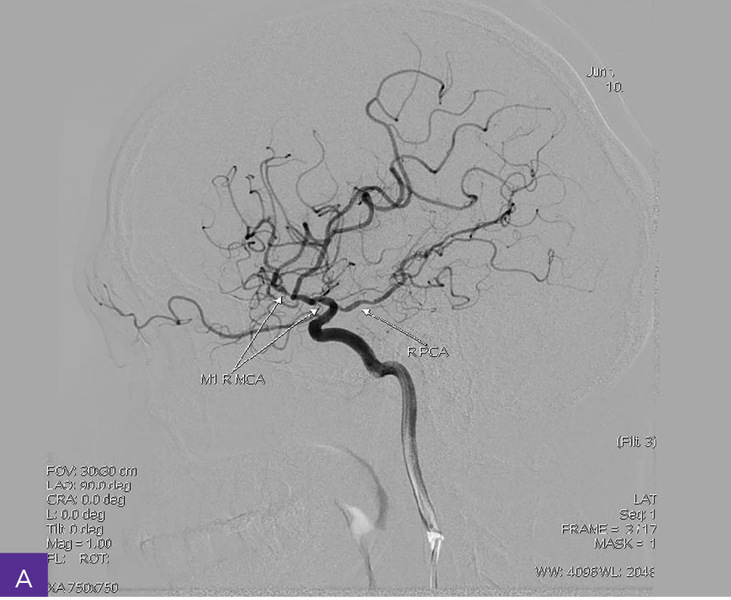

Rycina 4A-C. Cyfrowa angiografia subtrakcyjna (DSA). Widoczna przewlekła niedrożność nadklinowych odcinków obu tętnic szyjnych wewnętrznych, z wzorcem unaczynienia końcowego typu moyamoya, niedrożnością odcinków M1 obu tętnic środkowych mózgu, hipoplazją odcinków A1 obu tętnic przednich mózgu i krążeniem obocznym

Diagnostykę poszerzono o badanie cyfrowej angiografii subtrakcyjnej (DSA – digital subtraction angiography), która uwidoczniła przewlekłą niedrożność nadklinowych odcinków obu tętnic szyjnych wewnętrznych o nieznanej etiologii, z wzorcem unaczynienia końcowego typu moyamoya, niedrożnością odcinków M1 obu tętnic środkowych mózgu, hipoplazją (i/lub zastępczą neoangiogenezą) odcinków A1 obu tętnic przednich mózgu i krążeniem obocznym – głównie przez kolaterale obwodowe obu tętnic tylnych mózgu, po stronie prawej wspomaganym przez napływ z tętnicy oponowej środkowej i ocznej (ryc. 4).